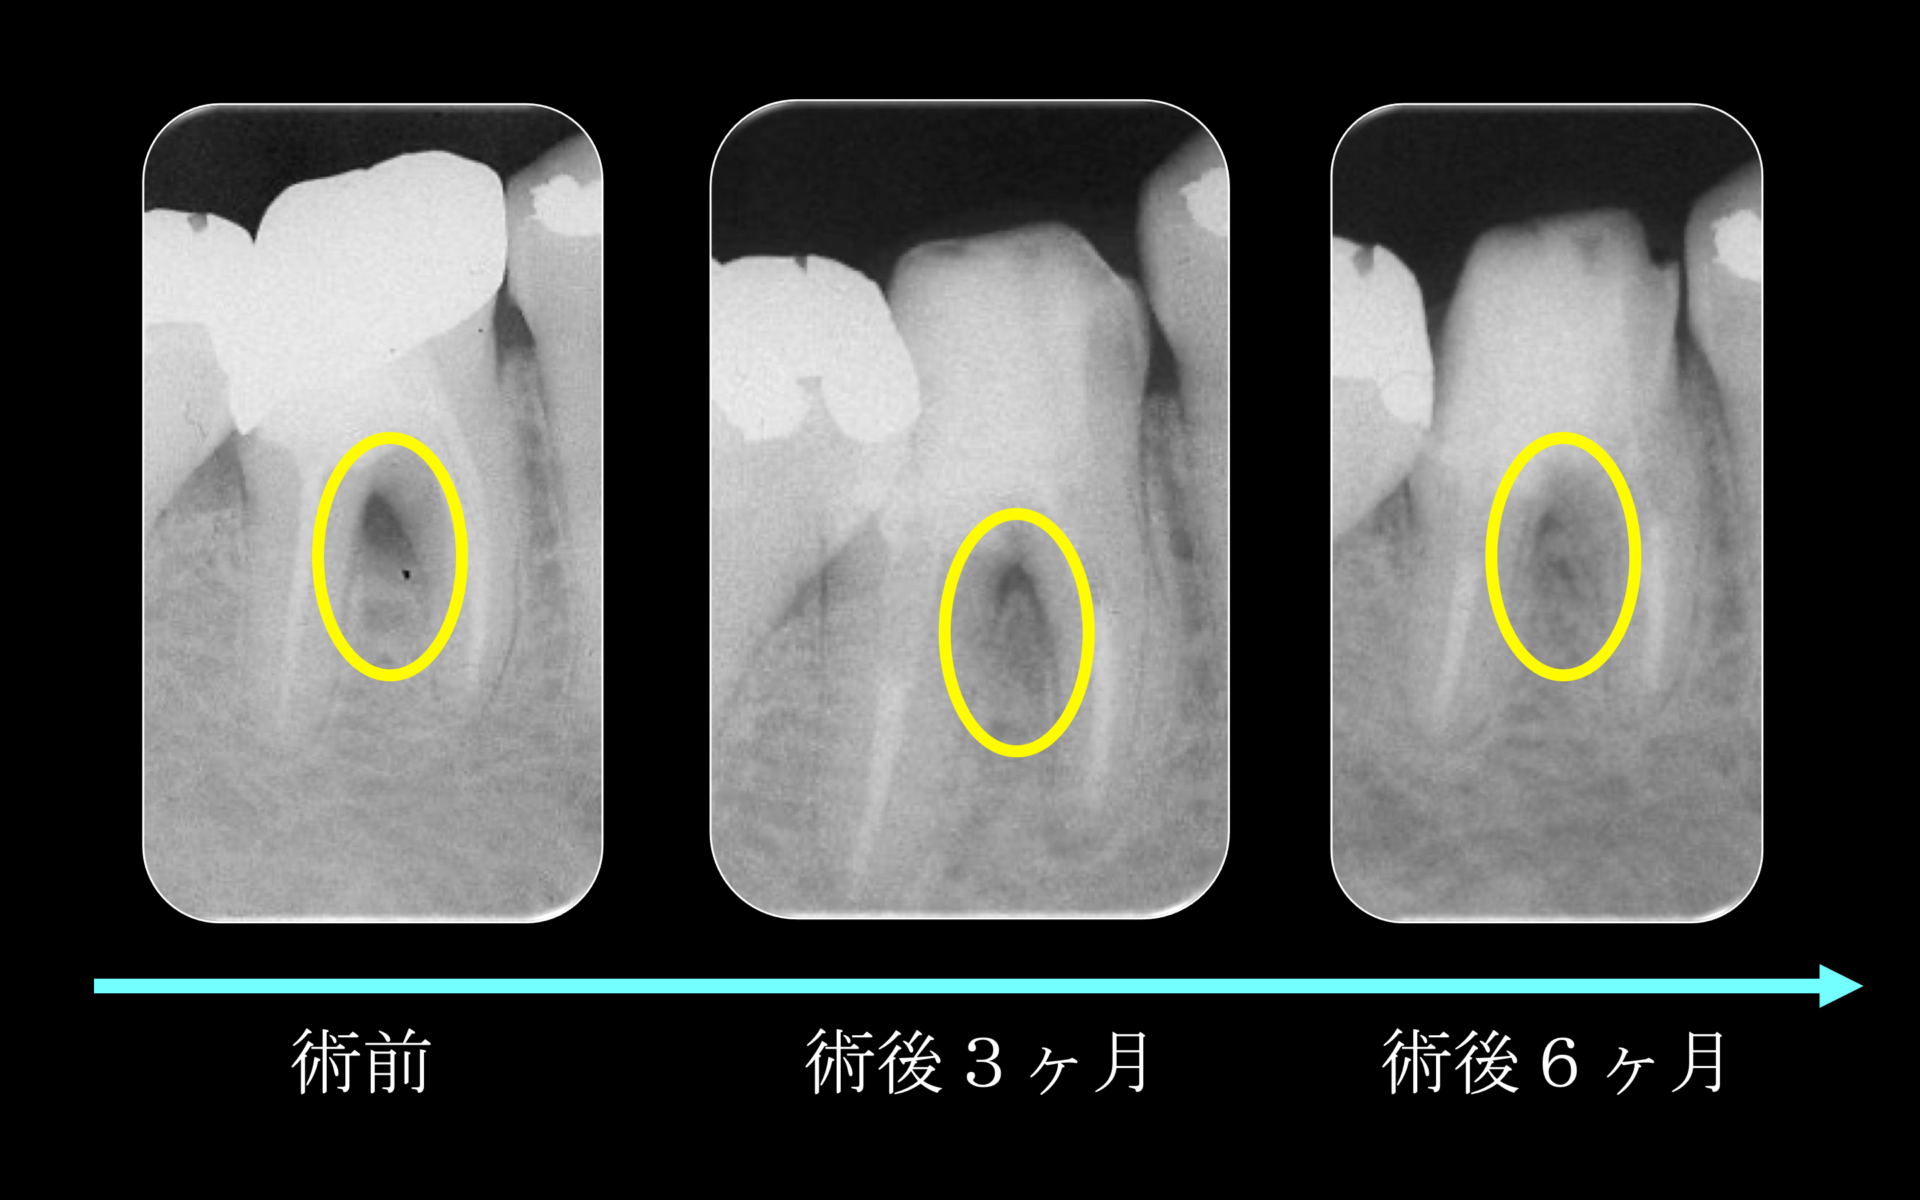

術後はレントゲン撮影により経過観察。初診時のレントゲンにあった黄色の円で囲っている黒い部分の病変は、経過を追うにつれ、病変が小さくなり、骨が再生されてきているのが分かる。歯周外科(再生療法)などは行なっておりません。

術後1年。レントゲン所見より黒い部分(病変)か消失し、完全に骨が再生されている(右図)被せ物はフルジルコニアクラウン(左図)